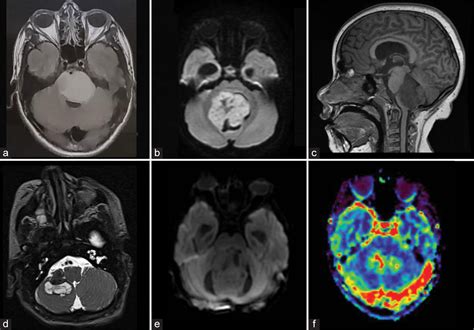

• Neuroimaging studies: Magnetic Resonance Imaging (MRI) or Computed Tomography (CT) scans to visualize the brain and identify any structural abnormalities.

• Neuroimaging studies: To identify biomarkers that can predict the onset and severity of PFS.